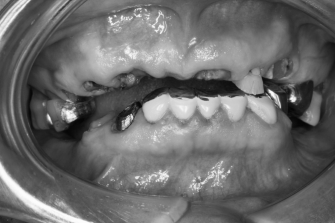

◎左写真 初診時

歯を抜いたまま、差し歯が取れまま放置されていたそうですが

いよいよ噛めなくなったので治療をされたいと来院されました。

根が完全に折れてしまったり、虫歯が進行しすぎている歯は

残念ながら抜歯になりますが、がんばって通っていただき

残せる歯はしっかり残して被せて、

歯がないところは保険内の入れ歯を入れることになりました。